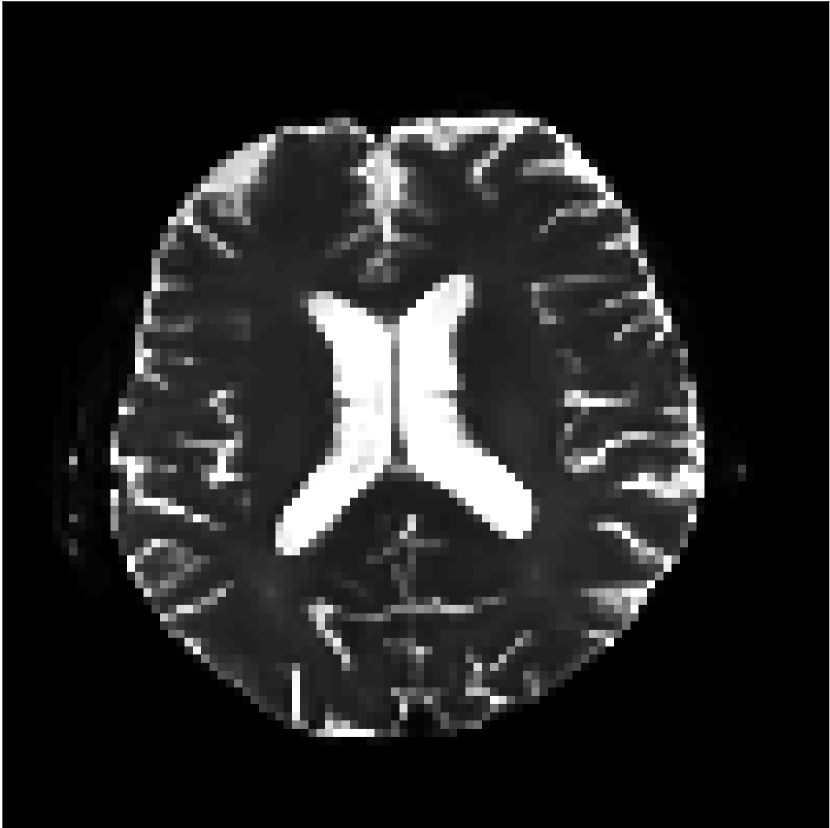

Figure 9 shows parameter maps for the different methods without partial Fourier (No PF) and with 5/8ths partial Fourier (5/8 PF). Mean diffusivities calculated from the raw DWI data (Raw) show notable noise and Gibbs ringing artifacts, while this is substantially removed with the state-of-the-art (SoA) method. However, the state-of-the-art method begins to lose its ability to compensate for the Gibbs ringing and resolution loss when partial Fourier is utilized in the acquisition. The effects of partial Fourier increases are primarily evident in the enlargement of the lateral ventricles and the presence of black lines in the vicinity of the lateral ventricles. The MCNN model is able to compensate somewhat for the ringing effects, but begins to introduce substantial artifacts at the 5/8ths partial Fourier factor, whereas the CCNN model continues to give high-quality mean parameter maps across all PF factors.

Raw

SoA

MCNN

Standard PF

CCNN

b=0𝑏0b=0 s/mm2

Refer to caption

No PF

MD, μ𝜇\mum2/ms

5/8 PF

FA

MK

Figure 9: Parameter maps from various methods (with CSF masks for FA and MK). At the top are shown the b=0𝑏0b=0 images from Raw, state-of-the-art (SoA), MCNN, standard partial Fourier, and CCNN methods. Rows 2 and 3 show results for mean diffusivity, rows 4 and 5 show results for fractional anisotropy, and rows 6 and 7 show results for mean kurtosis. The SoA method and both deep learning methods perform well without partial Fourier acceleration; however, at the 5/8ths partial Fourier factor, substantial artifacts are present for all methods other than the CCNN method.

Similar trends are observed in the other diffusion parameter maps.